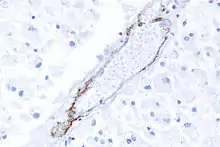

The definitive test is sequencing the whole Notch 3 gene, which can be done from a sample of blood. However, as this is quite expensive and CADASIL is a systemic arteriopathy, evidence of the mutation can be found in small and medium-size arteries. Therefore, skin biopsies are often used for the diagnosis.[13][14]